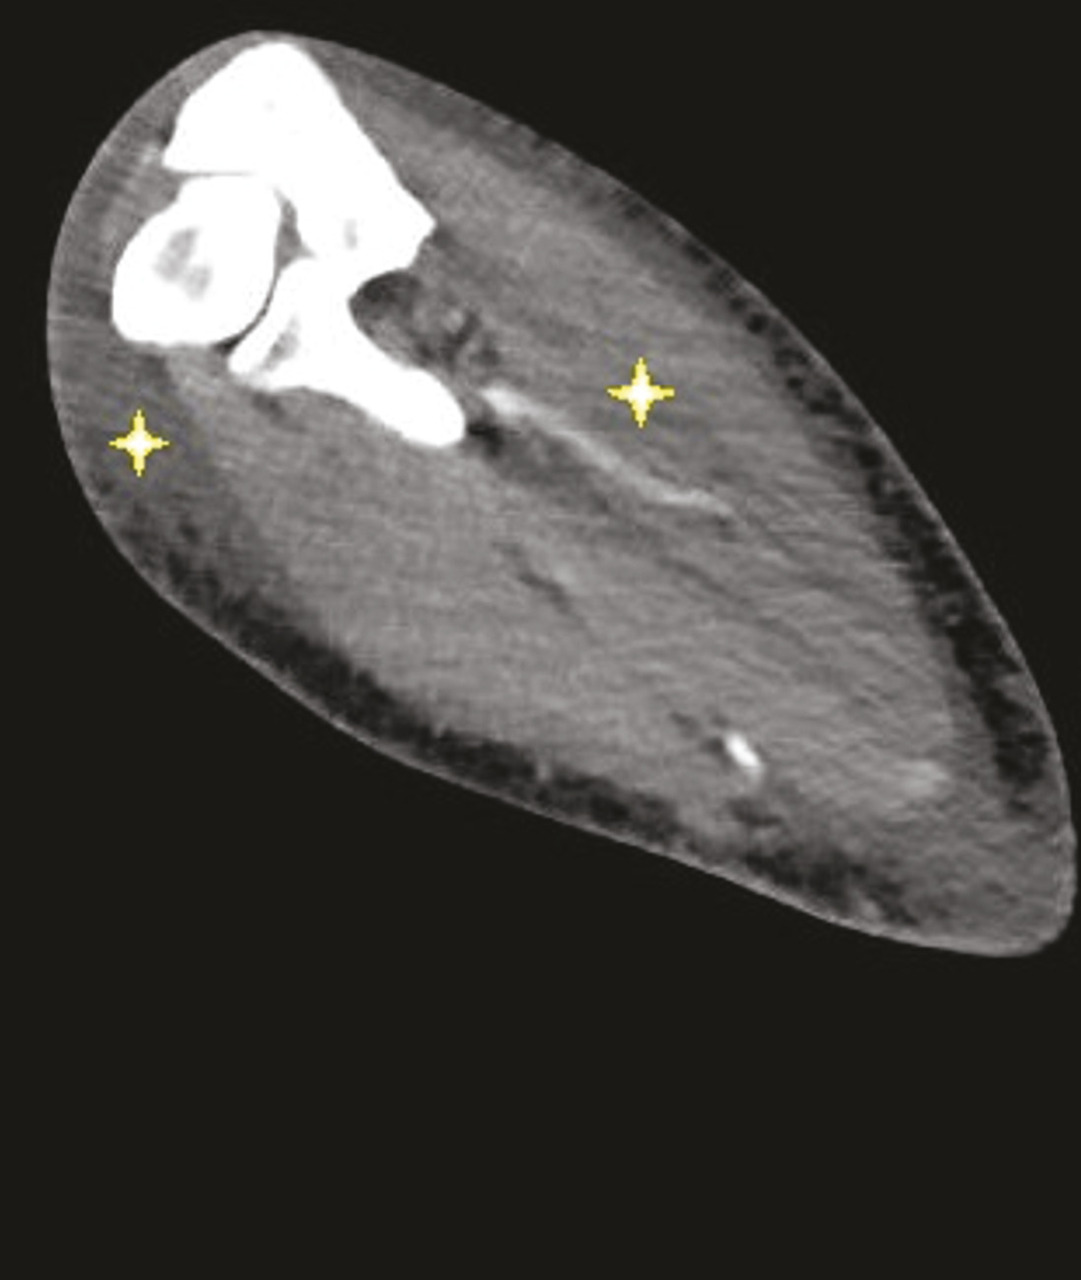

Image tomodensitométrique montrant un œdème prédominant au niveau des loges musculaires de l’avant-bras et des parties molles sous-cutanées en profondeur, adjacent aux fascias musculaires. Le DOMS, douleurs musculaires d’apparition retardée, ou courbatures, décrit une entité de dommages musculaires ultrastructuraux. Ils sont dus à un exercice excentrique ou des activités sportives non familières, à l’origine d’une réponse inflammatoire locale qui participe à l’accumulation de liquide interstitiel et à la formation d’un œdème intramusculaire.